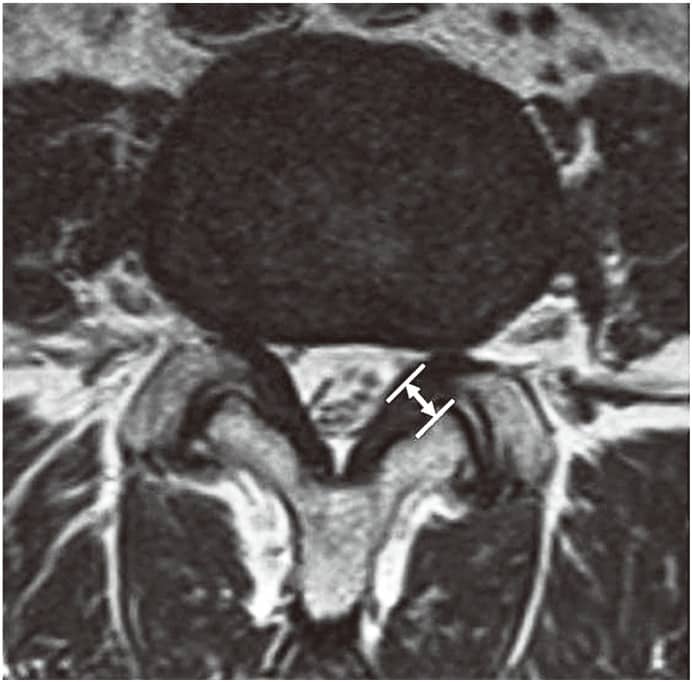

Ligamentum Flavum Kalınlaşması Nedir? Cerrahi Olmayan Tedavi Seçenekleri Bu makale, ligamentum flavum hipertrofisinin tanımı, nedenleri, belirtileri ve en iyi cerrahi olmayan seçenekler hakkında derinlemesine bilgi sunmaktadır. Fizyoterapi yöntemleri, ligamentum flavum hipertrofisini azaltabilir. Ligamentum Flavum Hipertrofisi Tanımlandı [...]

Boyun Fıtığı Belirtileri Nelerdir? Boyun fıtığı, tıbbi adıyla servikal disk herniasyonu, boyun bölgesindeki omurlar arasında bulunan disklerin zedelenmesiyle ortaya çıkan bir durumdur. Bu diskler, omurlar arasında yastıkçık görevi görür ve omurganın esnekliğini sağlar. Diskin dış bölgesindeki yırtılma sonucu iç kısımdaki [...]